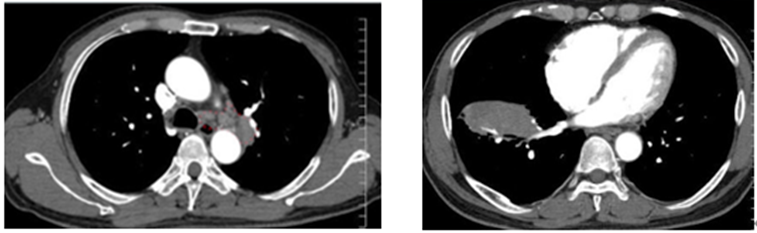

明らかな異常陰影ですので、悪性腫瘍も疑い造影CTを施行します。

所見としては、大動脈周囲リンパ節腫脹が確認できます。右腫瘤影(腫瘤の内部に血管が見えており、固形腫瘍の可能性下がる)を認め、リンパ腫やリンパ増殖性疾患を疑い生検します。